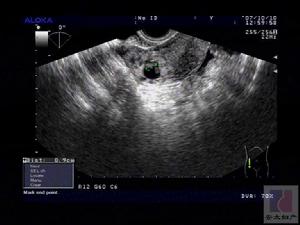

9.陰道或盆腔B超了解子宮、附屬檔案情況,排除婦科器質性疾病。